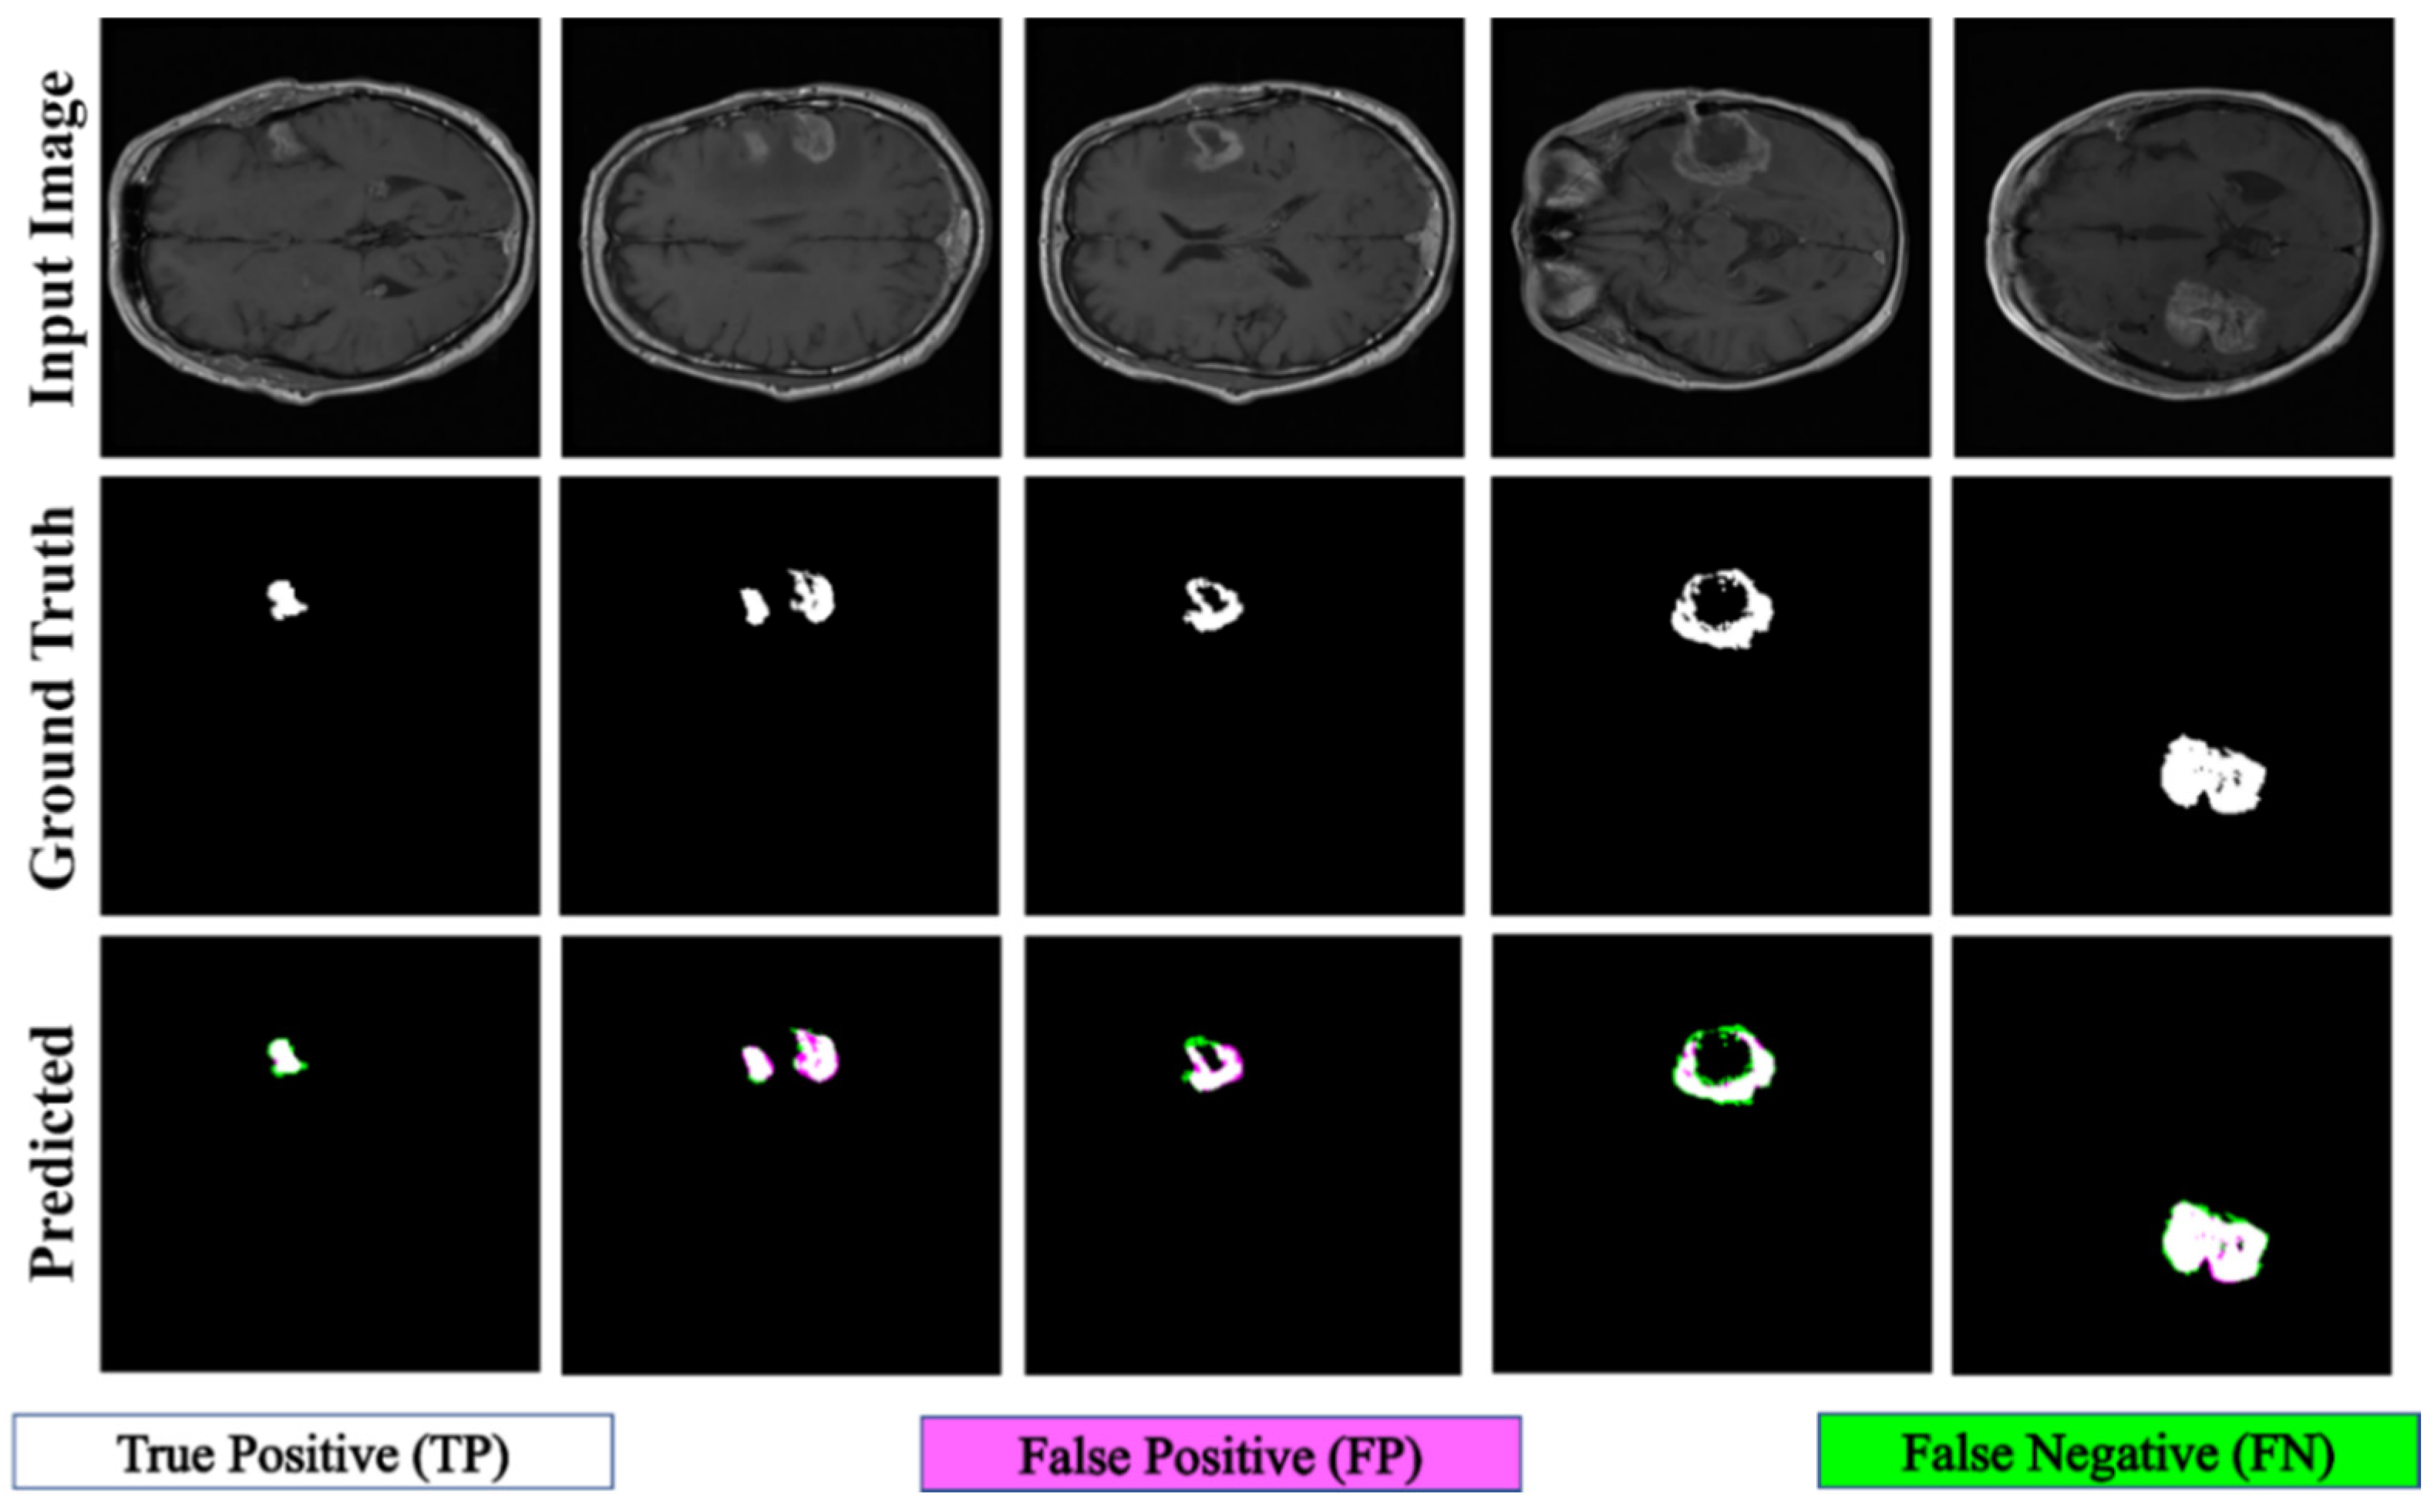

Figure 7 displays the qualitative results of ET segmentation performed using the proposed PFA-Net within a homogeneous dataset. In the case of TC segmentation, our proposed model outperforms all baseline models and attains the first position with a significant margin of 1.22% from the second-ranked method [42], as indicated in Table 10. Figure 8 displays the qualitative results of the TC segmentation performed by the proposed PFA-Net within a homogeneous dataset. In the case of WT segmentation, our proposed model outperforms all baseline models and attains the first position with a significant margin of 0.42% from the second-ranked method [45], as listed in Table 11. Figure 9 displays the qualitative results of the WT segmentation performed by the proposed PFA-Net within a homogeneous dataset.

Figure 7.

Qualitative results of the proposed PFA-Net for the segmentation of enhancing tumor (ET).

Figure 8.

Qualitative results of the proposed PFA-Net for the segmentation of tumor core (TC).

Figure 9.

Qualitative results of the proposed PFA-Net for the segmentation of whole tumor (WT).

The proposed PFA-Net demonstrated superior qualitative visual results for both homogeneous and heterogeneous dataset analysis in a challenging environment. Figure 16 illustrates the correct segmentation results for homogeneous dataset analysis with three segmentation masks, including ET, TC, and WT, and for heterogeneous dataset analysis. In detail, the first row of Figure 16 visually highlights the challenges in analyzing BT scans, such as a minute tumor in the case of ET, having only the border edge of tumors for TC, the amalgamation of tumor features with background features for WT, and the enhancement of edges by tumor-like features in the heterogeneous dataset analysis. Despite these challenges, PFA-Net demonstrates superior performance for all cases. However, the performance of PFA-Net is constrained due to diffuse and irregular characteristics, non-specific enhancement, diverse distribution, heterogeneity, and the coexistence of different tumor components, as shown in Figure 17. This indicates that while PFA-Net excels in certain scenarios, there are specific tumor configurations that present challenges to its overall performance.

Figure 16.

Examples of correct segmentation for homogeneous dataset analysis with three segmentation masks: (a) ET mask, (b) TC mask, (c) WT mask, and (d) for heterogeneous dataset analysis.